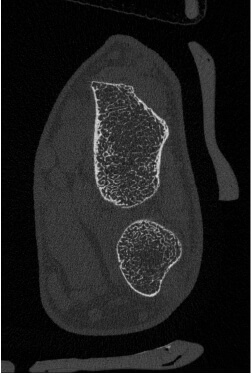

HR-pQCT装置(高解像度の末梢骨用の定量的CT装置)

高解像度末梢骨用定量的CT(high-resolution peripheral quantitative CT:HR-pQCT)は,前腕や下腿の骨を高解像度で撮影し、骨の内部構造を三次元的に評価することができる最先端計測機器です。従来の骨密度検査(DEXA)では評価しきれなかった、「骨の質」や骨の細かい構造の変化を捉えることができ、より高度な骨粗鬆症の診断・治療効果の判定に役立ちます。HR-pQCTは研究機関や専門病院など、限られた施設でしか導入されておらず、先進的な骨の評価を受けられることが当院の強みのひとつです。大学や研究機関とも共同研究を行っています。実際に患者さんの骨の状態を詳しく評価し、テーラーメードの骨の治療を行うようにしています。

【撮影画像】

手関節部

(20代) -

手関節部

(50代骨粗) -

足関節部

(20代) -

足関節部

(60代骨粗)